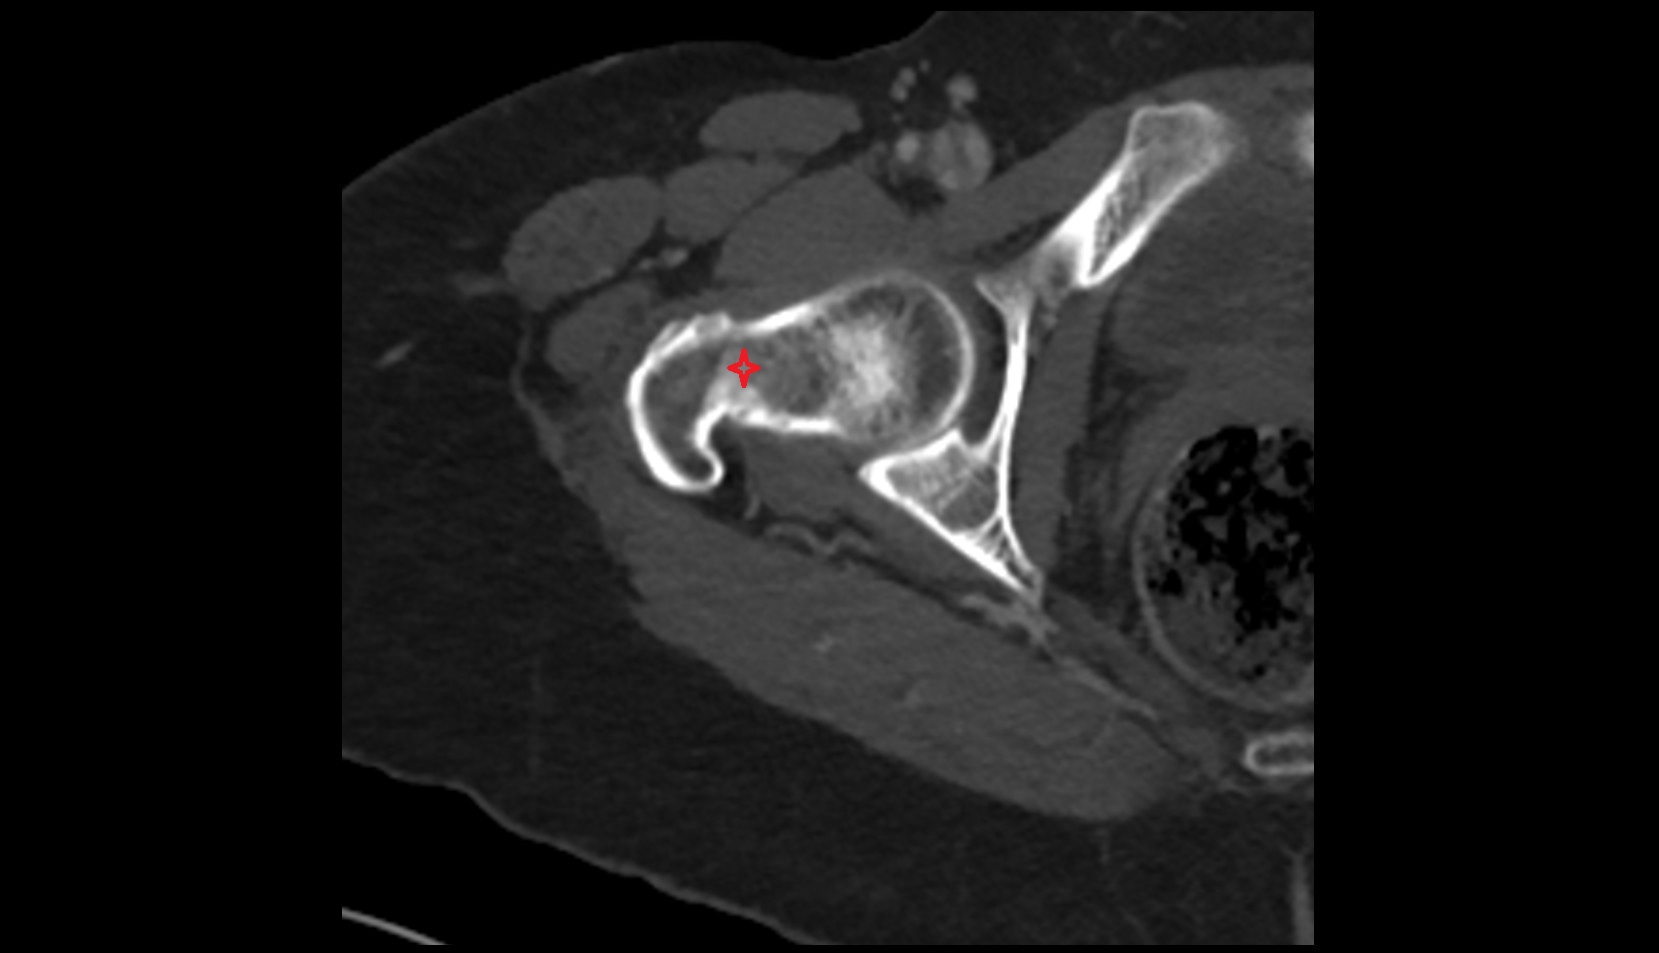

- Acetabular margin (Acetabular rim)

- Acetabulum

- Head of femur

- Neck of femur

- Acetabular labrum

- Articular capsule of hip joint

- Hip joint